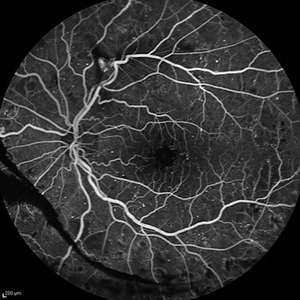

Behcet's Disease Behcet's DiseaseMar 13 2013 by Hamid Ahmadieh, MD Early phase FA of the left eye of a 23-year-old man with retinal vasculitis due to Behcet's disease . Photographer: Solmaz Shahmohammad, Negah Eye Center, Tehran Imaging device: Heidelberg Spectralis Condition/keywords: retinal vasculitis

Behcet's Disease Behcet's DiseaseMar 13 2013 by Hamid Ahmadieh, MD Mid phase FA of the left eye of a 23-year-old man with retinal vasculitis due to Behcet's disease . Photographer: Solmaz Shahmohammad , Negah Eye Center, Tehran Imaging device: Heidelberg Spectralis Condition/keywords: retinal vasculitis